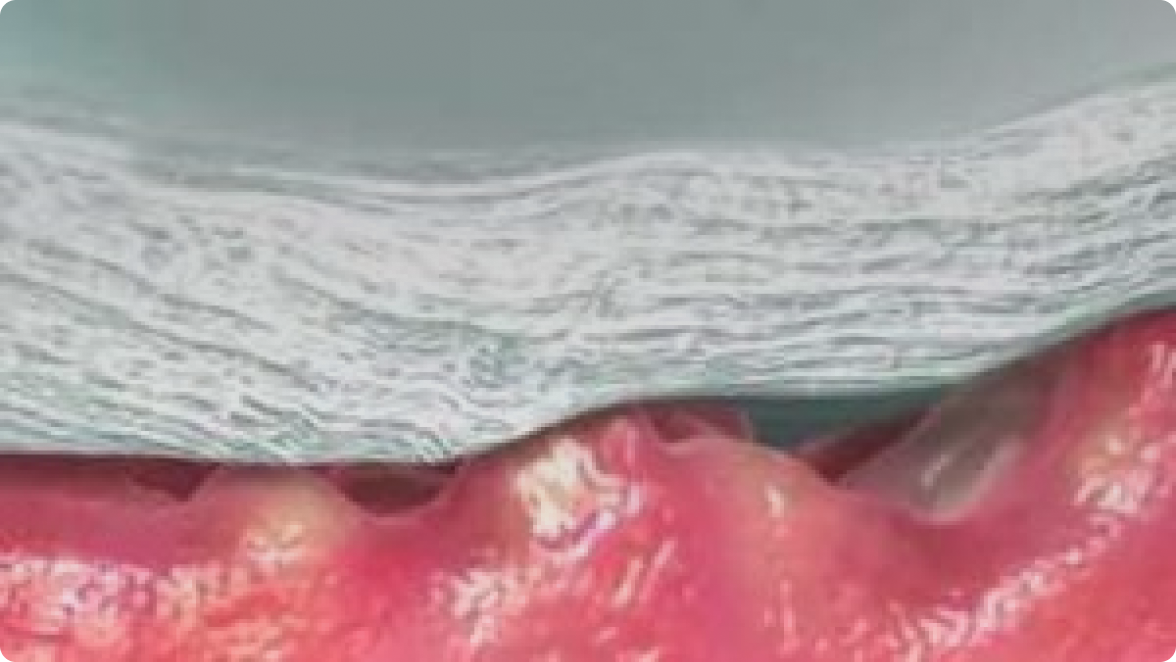

Hjälper till att skydda huden runt såret och minska risken för maceration4,5

Mikrokonturer till sårbädden*8

Intim kontakt

Låser in

Konturer